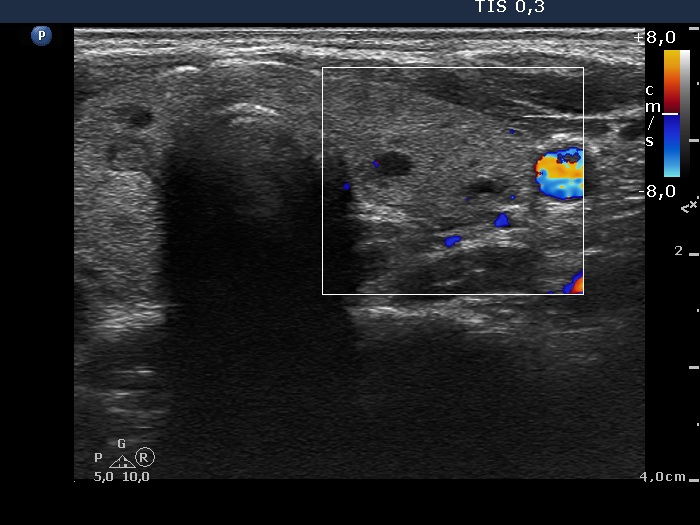

Consecutively operated patients with autoimmune thyroid disease - case 21 (1083) (ultrasonographic picture 8)

Left lobe, transverse scan, color Doppler mode. The vascularization is scanty.